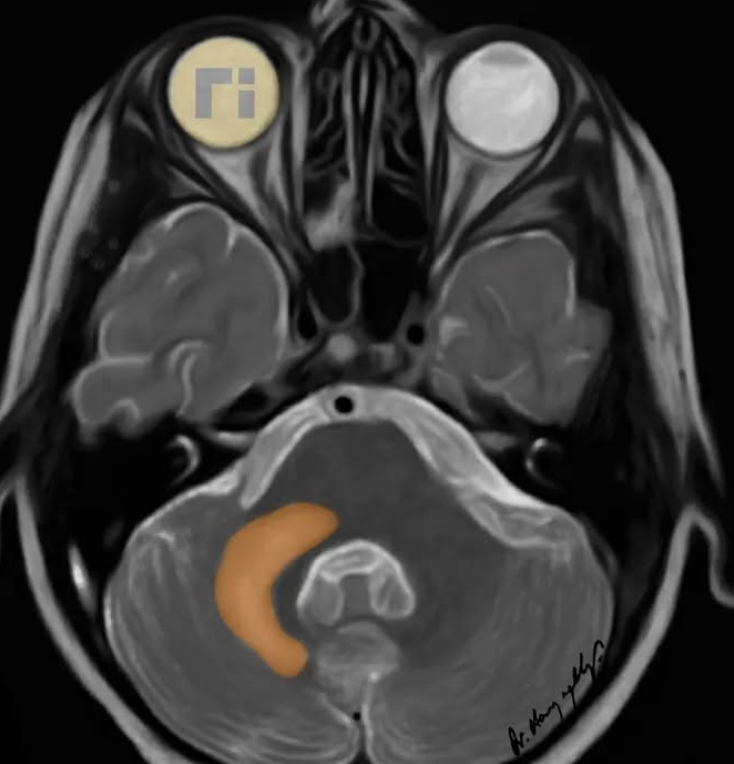

• Shrimp sign - T2 hyperintensity of the cerebellar white matter but which spares the dentate nucleus

Image showing abnormally hyperintense dentate nuclei.

Note: This image is not PML it just shows anatomy of dentate nuclei well since they are so abnormally bright here,